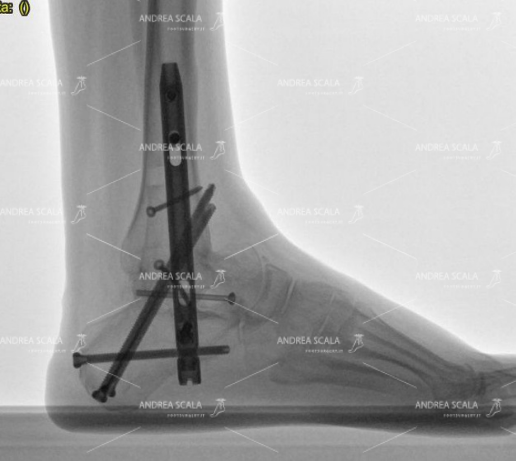

Fortunatamente oggi c’è un’alternativa che consente la ripresa ottimale dei movimenti. Il dottor Andrea Scala, infatti, propone una tecnica chirurgica alternativa e personale che impiega diversi modelli di protesi su misura, il cui design e le cui prestazioni sono di livello molto elevato.

Abbiamo già parlato della differenza tra l’artrodesi e l’operazione di protesi di caviglia effettuata dal dottor Andrea Scala, con il suo metodo personale, sottolineando i vantaggi del secondo intervento rispetto al primo. Il dottor Andrea Scala, non si affida ad un solo marchio di protesi di caviglia, ma combina in maniera autonoma design e materiali diversi, anche di brand differenti, per rendere la protesi unica, modellata su misura in base alle necessità del paziente al quale dovrà essere impiantata la protesi di caviglia.

Questo è molto importante da sottolineare perché evidenzia il fatto che il dottor Andrea Scala non è legato a marchi, ma sceglie i modelli di protesi di caviglia solo in base alle reali necessità e al benessere dei suoi pazienti. Addirittura può combinarli finendo per realizzare il “modello” perfetto ed ideale che rispecchi tutte le caratteristiche indispensabili per permettere ad un paziente di tornare a svolgere le sue azioni quotidiane il più presto e nel modo più naturale possibile. Grazie alla protesi personalizzata, che durerà diversi decenni, il soggetto dimenticherà il dolore e recupererà sin da subito le proprie abitudini.

La sua è una tecnica sperimentata negli anni con grande efficacia: la comprovata esperienza e i risultati positivi hanno permesso al dottor Andrea Scala di farsi conoscere a livello nazionale e di diventare uno dei migliori chirurghi ortopedici del piede in Italia, scelto anche dai piloti dell’aeronautica militare.